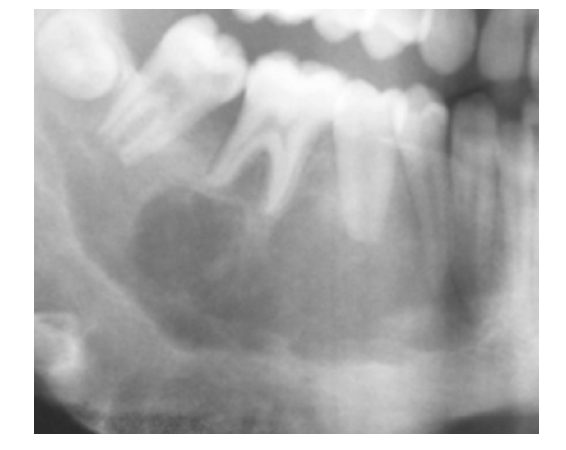

Aneurysmal Bone Cyst

Pseudocyst w/ blood-filled spaces

Posterior Mandible

* Multilocular Radiolucency:

* Expansile

Tx: Fine Needle Aspiration 1st (Blood=Confirms Dx)

* Excision